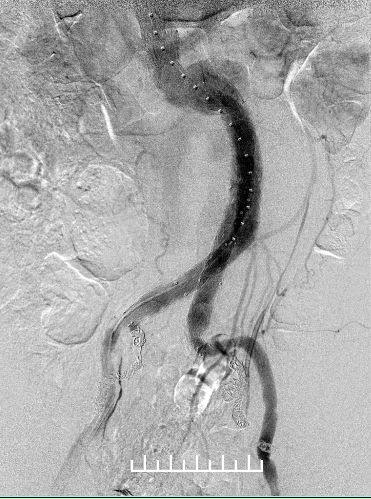

再次造影:右侧髂支未显影!!!

是否近端原因,扩张一下

造影显示同样的结局

鞘管逆行造影,支架远端没问题,右侧股动脉搏动也正常。考虑血管扭曲,鞘管影响所致。

所以我们拔出右侧导管,缝合穿刺点。再次造影:显影良好,流速正常。

手术结束,送监护室。术中出血50ml,手术时间6个小时。术后1天拔管,48小时肛门排气排便,返回病房。